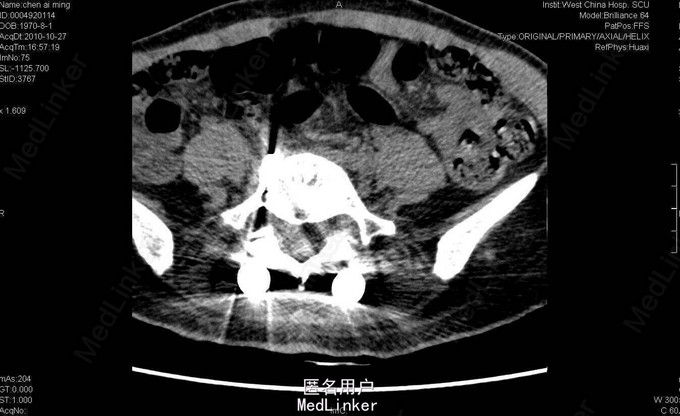

女,40岁2月,因“腰部反复疼痛2+年,加重伴双下肢疼痛、麻木1+年”入院。视:脊柱外观无畸形,皮肤未见红肿、皮疹、破溃、色斑等,无明显包块。触:腰5骶1椎棘突压痛,椎旁肌压痛,无放射痛。腰骶部感觉麻木。双下肢小腿外侧及足背感觉减退,右侧明显,其余肢体感觉正常,肌张力正常。鞍区右侧感觉减退。双下肢足背动脉搏动好。皮温正常。双膝腱减弱,踝阵挛、髌阵挛(-),巴氏征(-),右下肢直腿抬高试验(30°),直腿抬高加强试验(+),左下肢直腿抬高试验(-)。“4”字征阴性。动量:腰部不能屈伸活动,侧弯可,双下肢活动度正常,四肢肌力正常。CT及MRI:腰5骶1椎间盘脱出,腰4-5椎间盘轻度膨出,硬膜囊受压;腰5骨质增生。腰5骶1椎间盘突出症伴小关节退变。双侧椎板开窗腰5骶1椎间盘髓核摘除、内固定术。